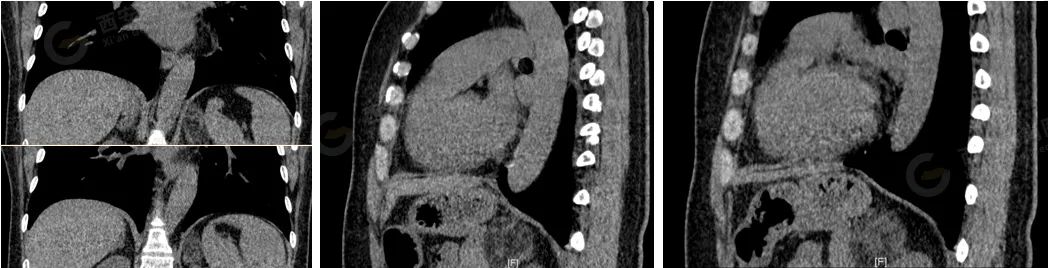

女,47 岁。无明显症状于高尚医学影像诊断中心体检。

左侧肾上腺区可见一混杂密度肿块影,边界尚清楚,大小约 3.4×3.8 cm,内部以脂肪成分为主,可见少许实性等密度影,与肾上腺关系密切。考虑来源于肾上腺肿瘤,髓样脂肪瘤可能性大。

手术切除病理结果:髓样脂肪瘤。